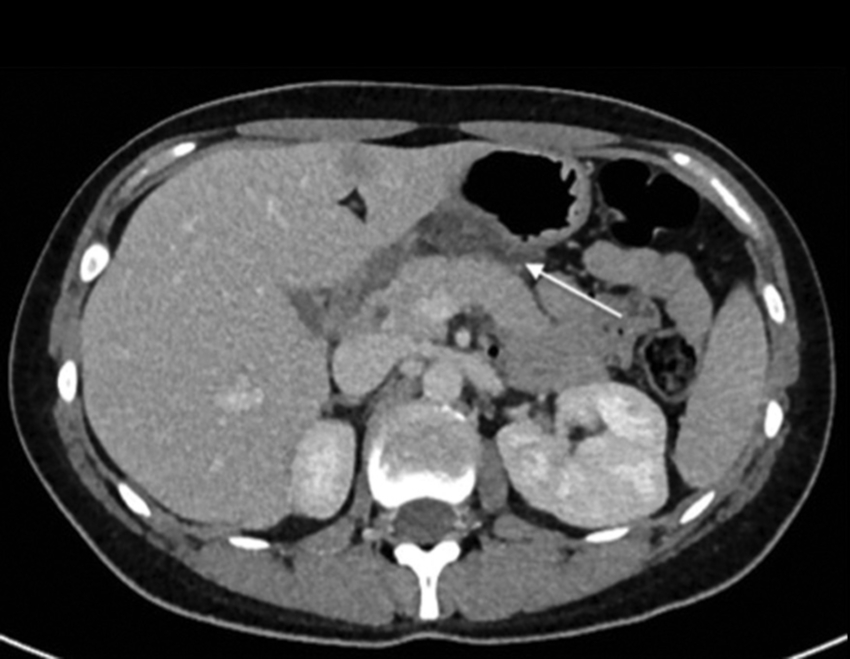

Comunicamos el caso de una mujer de 29 años, sin antecedentes mórbidos de importancia, que consultó por un cuadro de 24 horas de evolución de distensión abdominal y dolor epigástrico, que luego se hizo difuso, sin fiebre. Al examen físico destacaba dolor a la palpación abdominal, preferentemente en el hemiabdomen superior. Se le realizaron exámenes de laboratorio en los que solo se objetivó elevación de la proteína C reactiva con un valor de 14,3 nmol/l. Se decidió estudiar el dolor abdominal con una ecografía, en la que se identificó un área de tejido ecogénico lobulado, relativamente bien delimitado, situado entre el páncreas y la cara posterior del cuerpo y del antro gástrico (Fig. 1), compatible con un proceso inflamatorio del tejido adiposo peripancreático cuya etiología no se precisó. Ante estos hallazgos, se decidió complementar el estudio con una tomografía computada (TC) de abdomen y pelvis con contraste, en la que se confirmó la presencia de un aumento de la densidad del tejido adiposo comprendido entre el páncreas y el estómago, específicamente adyacente a la curvatura menor del estómago y pared posterior (Figs. 2 y 3). El tejido adiposo en relación con la mayor parte de la curvatura mayor presentaba densidad normal. Ante estos hallazgos, se diagnosticó un infarto del epiplón menor, sin signos de complicación, por lo que se decidió manejo con analgesia y controles seriados. La paciente tuvo una evolución favorable con un control a los dos meses con una nueva TC de abdomen y pelvis con contraste, en la que se observó una marcada disminución del aumento de volumen y densidad del omento menor en comparación al examen previo (Fig. 4).

La presentación clínica generalmente es dolor abdominal con sensibilidad y algunas veces con signos de irritación peritoneal. Las pruebas de laboratorio generalmente muestran una elevación leve de los parámetros inflamatorios. El diagnóstico clínico inicial depende de la localización de dolor y generalmente dentro de los diagnósticos diferenciales destacan la apendicitis, la colecistitis y la diverticulitis3,4,5,6. Ecográficamente, la presentación clásica es la de una masa sólida, moderadamente hiperecogénica, no compresible y que se encuentra en íntimo contacto con el lóbulo hepático izquierdo, páncreas y estómago, los cuales no presentan alteraciones. En TC, la presentación es de una masa inflamatoria con densidad adiposa, bien circunscrita, rodeada de órganos normales3,4,5,6,8.